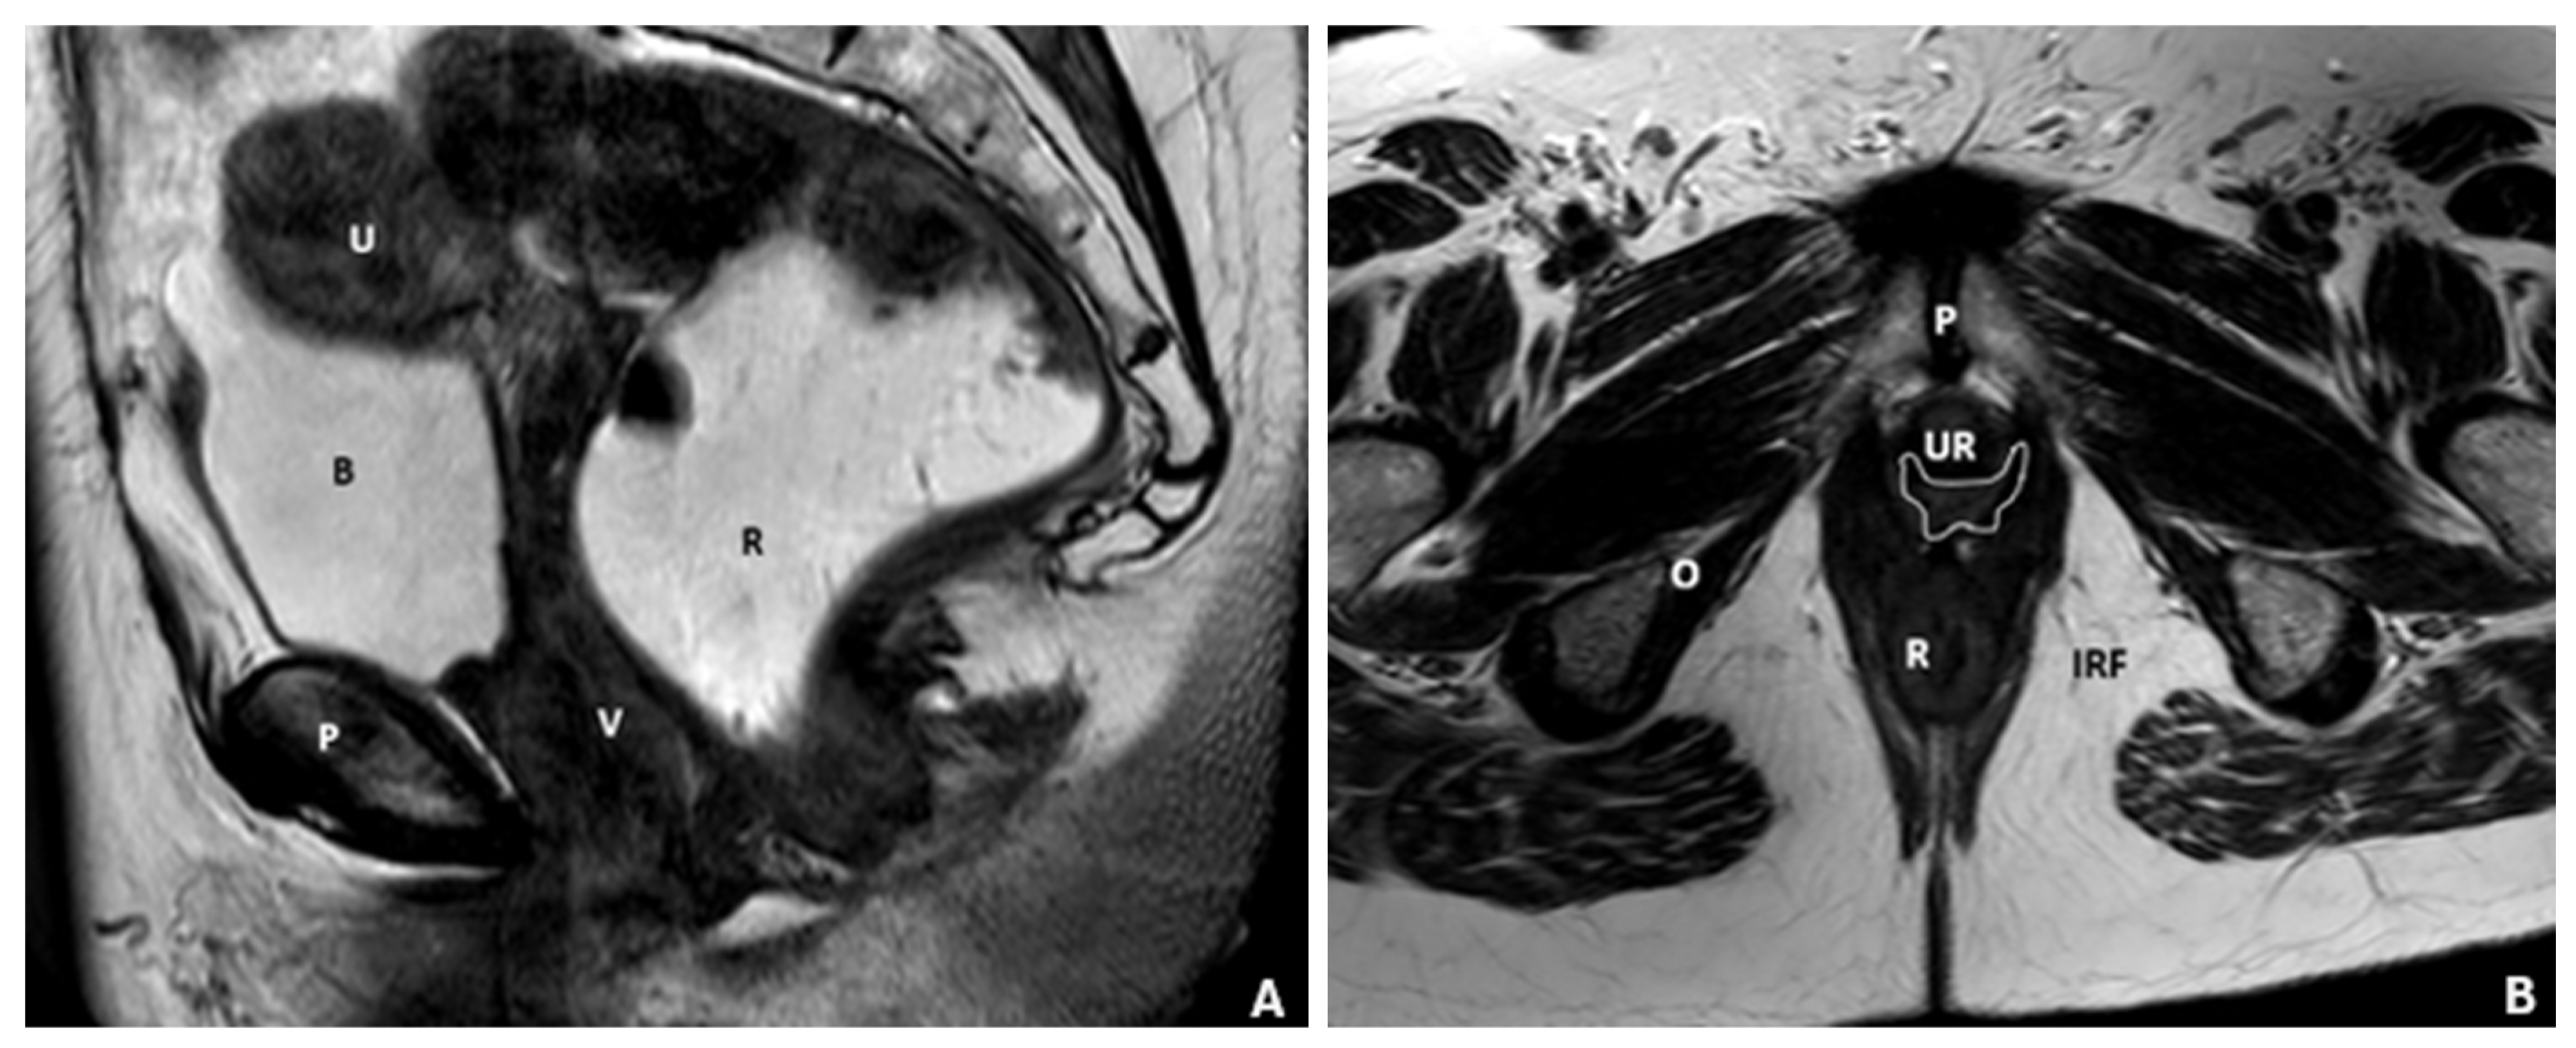

- Salvador, J.C.; Coutinho, M.P.; Venâncio, J.M.; Viamonte, B. Dynamic magnetic resonance imaging of the female pelvic floor-a pictorial review. Insights Imaging 2019, 10, 4. [Google Scholar] [CrossRef]

- Flusberg, M.; Kobi, M.; Bahrami, S.; Glanc, P.; Palmer, S.; Chernyak, V.; Kanmaniraja, D.; El Sayed, R.F. Multimodality imaging of pelvic floor anatomy. Abdom. Radiol. 2021, 46, 1302–1311. [Google Scholar] [CrossRef]